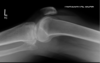

1. Peroneal nerve:

Segond Fracture Avulsion fracture of lateral tibial plateau Attachment site of LCL Sport injurie flexed knee + internal rotation + varus stress Oval shaped fragment adjacent to lat. Tibia plateau